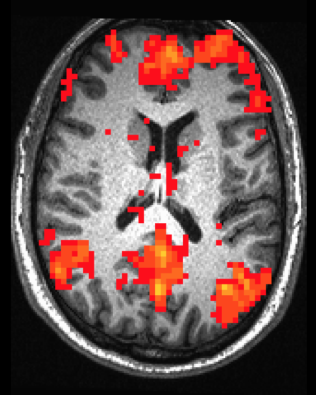

Seed-based Correlation Analysis (SCA) is one of the most common ways to explore functional connectivity within the brain. Based on the time series of a seed voxel (or ROI), connectivity is calculated as the correlation of time series for all other voxels in the brain. The result of SCA is a connectivity map showing Z-scores for each voxel indicating how well its time series correlates with the time series of the seed. Below is an example connectivity map showing correlated voxels based on a seed in the precuneus.

Astute readers will note that the pattern of connectivity mapped above closely resembles the anatomy of the Default Network. Indeed, SCA may be used to explore functional networks that share similar patterns of activity.